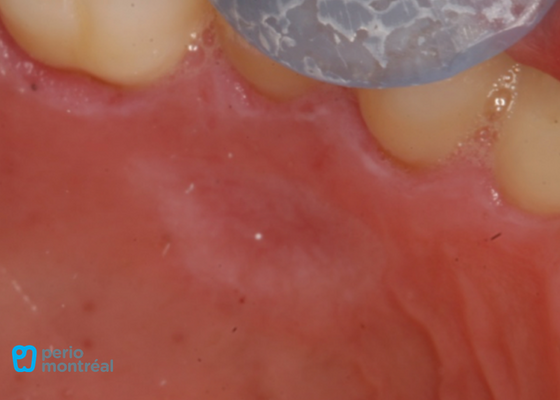

The recipient site is prepared following root planing of tooth #41 to decrease the root convexity. The donor tissue is harvested from the right palate.